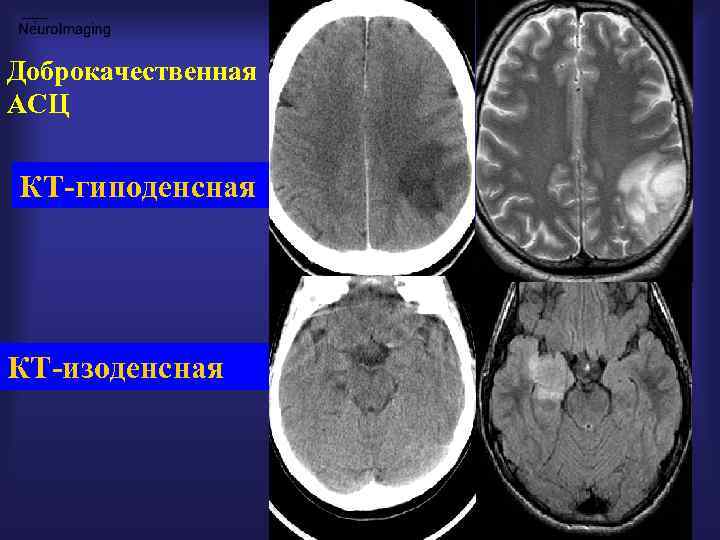

Доброкачественная АСЦ КТ-гиподенсная КТ-изоденсная